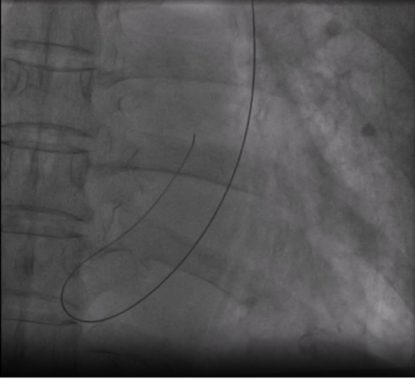

张卫泽副院长带领心内一科团队,通过完善血管超声检查精准评估下腔静脉血管路径正常,追踪患者既往心电检查结果确认无房室传导阻滞,与家属商议后决定采用心房无导线起搏器(雅培 Aveir AR)植入术式。

无导线起搏器体积仅胶囊大小(约 1.0cc),重量不足 2 克,通过导管直接植入心腔,无需切开皮肤或植入传统的电极导线,刚好解决了解剖变异问题。术中使用 Aveir AR 专用输送系统经右侧股静脉-下腔静脉血管途径顺利将起搏器送入右心房,并精准释放于右心耳,测试参数满意,术后心电监测记录到患者再次出现心脏停搏,起搏器及时启动帮助跳动,患者未发生不适症状。术后 24 小时程控起搏器阈值良好,工作状态无异常。患者头晕、心慌症状显著缓解,无需换药拆线,第三日即办理出院,如此效率,让患者及家属连连称赞。